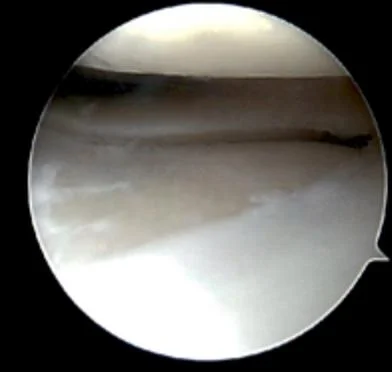

• Knee Arthroscopy

• Meniscal Repair